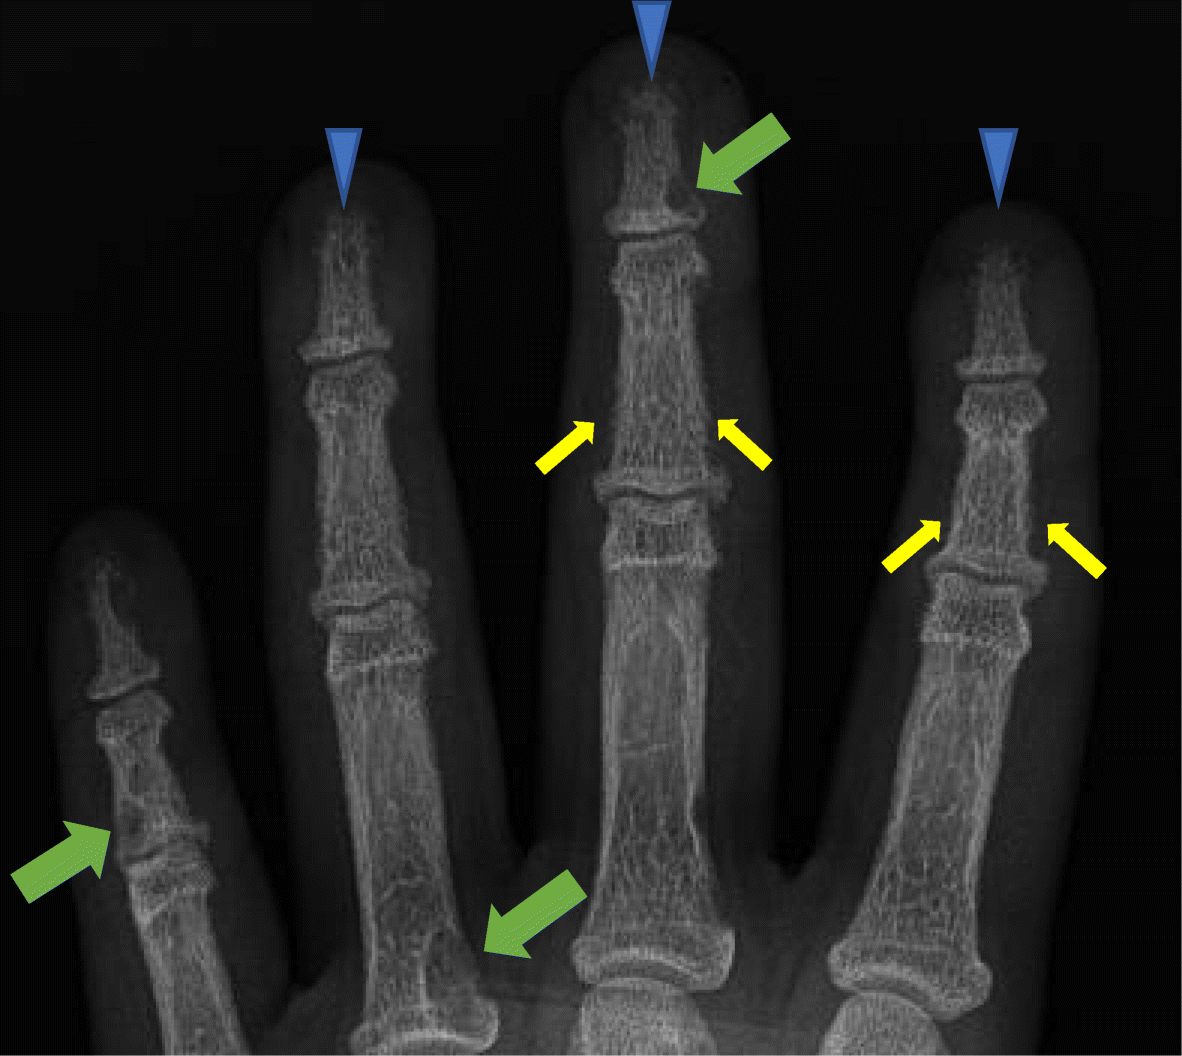

Frontal radiograph of the left hand in a 14 year old male patient with hyperparathyroidism demonstrates acro-osteolysis (arrowheads), subperiosteal resorption at the middle phalanges (small arrows), brown tumors (large arrows) and diffuse osteopenia